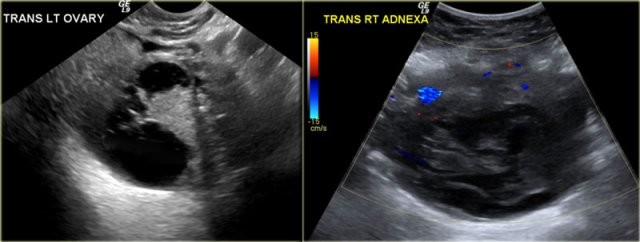

6 months later a follow-up MRI was performed.

The lesions are bright on T1-weighted images.

The bright signal persists on fat saturation indicating the presence of blood.

There is T2 shading consistent with a hemorrhagic lesion.

There is no enhancement.

The fluid-fluid level in the right ovarian lesion also confirms its cystic nature.

The fact that the lesions persist after 6 months makes bilateral endometrioma much more likely than hemorrhagic cysts.